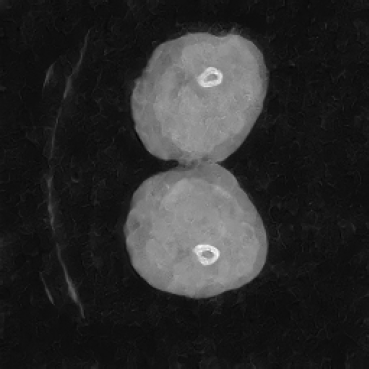

As shown in Figure 5, the generated slices exhibit high consistency across adjacent slices. The anatomical structures and semantic patterns are smoothly and coherently preserved between slices, indicating that our model is capable of generating 3D-consistent synthetic images rather than isolated 2D slices.